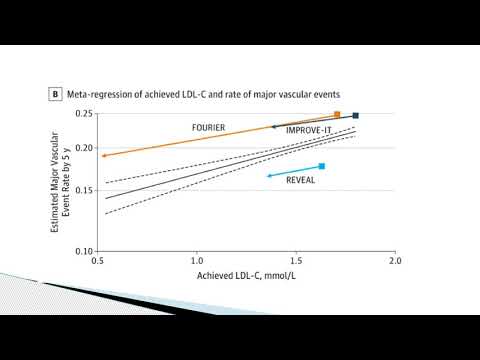

Eficacia y seguridad de promover un descenso de LDL colesterol en pacientes que inician con valores muy bajos. Dr. Mariano Napoli Llobera. Residencia de Cardiología. Hospital C. Argerich Buenos Aires